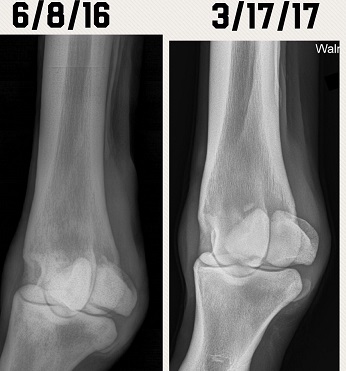

Just wanting to see if anyone had any opinions on these X-rays. Diagnosis was a fractured sesamoid bone. Before and after X-rays in the pics. Do they look any better? Does he have any hope for a barrel future? Anyone experienced this before? Completely sound in the pasture at this time. Has not been put back to work yet. Thanks man advance.

(xray 1.JPG)

(xray 2.JPG)

(xray3.JPG)

(6-1-16 side2.jpg)

Still looks like a chip is floating around in there.

How old is this horse? I do see what looks like a bone chip floating around

The vet has said it has calcified some. He hasn't said anything about a chip in there. I don't know if it is something that will break off or just calcify and heal up in the next few years.